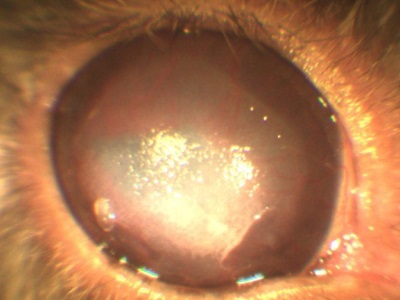

Atunci când diferite defecte ale corneei (eroziune, ulcer, traumatisme), creează edem, îngroșarea corneei, datorită cărora devine alb (opac).

eroziunea corneei, iepure

defecte corneene apar, atât din cauza traumei de factori externi, și fără ele. Genele patologici, pleoape volvulus (parțială și completă), keratoconjunctivita sicca, toate acestea conduc la o leziune a corneei (eroziuni ale corneei sau ulcere).

Este important să distingem aceste stări patologice, ca și tratamentul eroziuni, ulcere și leziuni datorate diferitelor motive diferite. Oftalmolog specialist cu experiență suficientă și echipament specializat pentru a ajuta la identificarea bolii, și cauza algoritmului de acțiune.